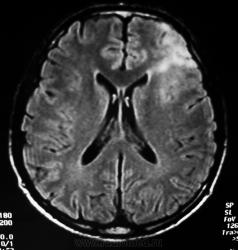

Мужчина 1961 г.р. Головные боли, учащение эпиприступов в последние полгода. В анамнезе в мае 2005г. оперирован по поводу астроцитомы левой лобной доли (биопсия - протоплазматическая астроцитома с анаплазией) в другом ЛПУ. МРТ там же перед операцией, через 6 мес и через 1,5 года (у нас нет МРТ). После операции проведена лучевая терапия 60 Гр.

Представляю КТ: нативное исследование 29.09.2010 и с контрастом 1.10.2010 + реконструкции. Направлен на КТ с диагнозом: рецидив опухоли?

Масс-эффект, латеральная дислокация 10 мм.

Ваше мнение? Можно ли трактовать обызвествления как последствия кровоизлияния, пертификаты?

МРТ ноябрь 2005:

Может, это "новая"? Я не могу объяснить наличие обызвествлений. Буду благодарна за любые ссылки по глиальным опухолям.

Рецидив в данном случае можно точно писать, хоть и контрастное вещество и не накапливает это ни о чем не говорит, одно надо понимать что фибриллярная и протоплазматическая астроцитомы редко когда они подвергаются полному нейрохирургическому удалению. Кальцинаты характерны для фибриллярной астроцитомы, у меня складывается картина вообще об фибрриллярно-протоплазматической астроцитоме.

5 летний период наблюдения свидетельствует о продолженном росте глиальной опухоли, была фаза клинической компенсации, перешедшая в декомпенсацию.

Спасибо! Родственники пациента мне отзвонились, повторно прооперирован, рецедив подтверждён, только гистологию они не знают.